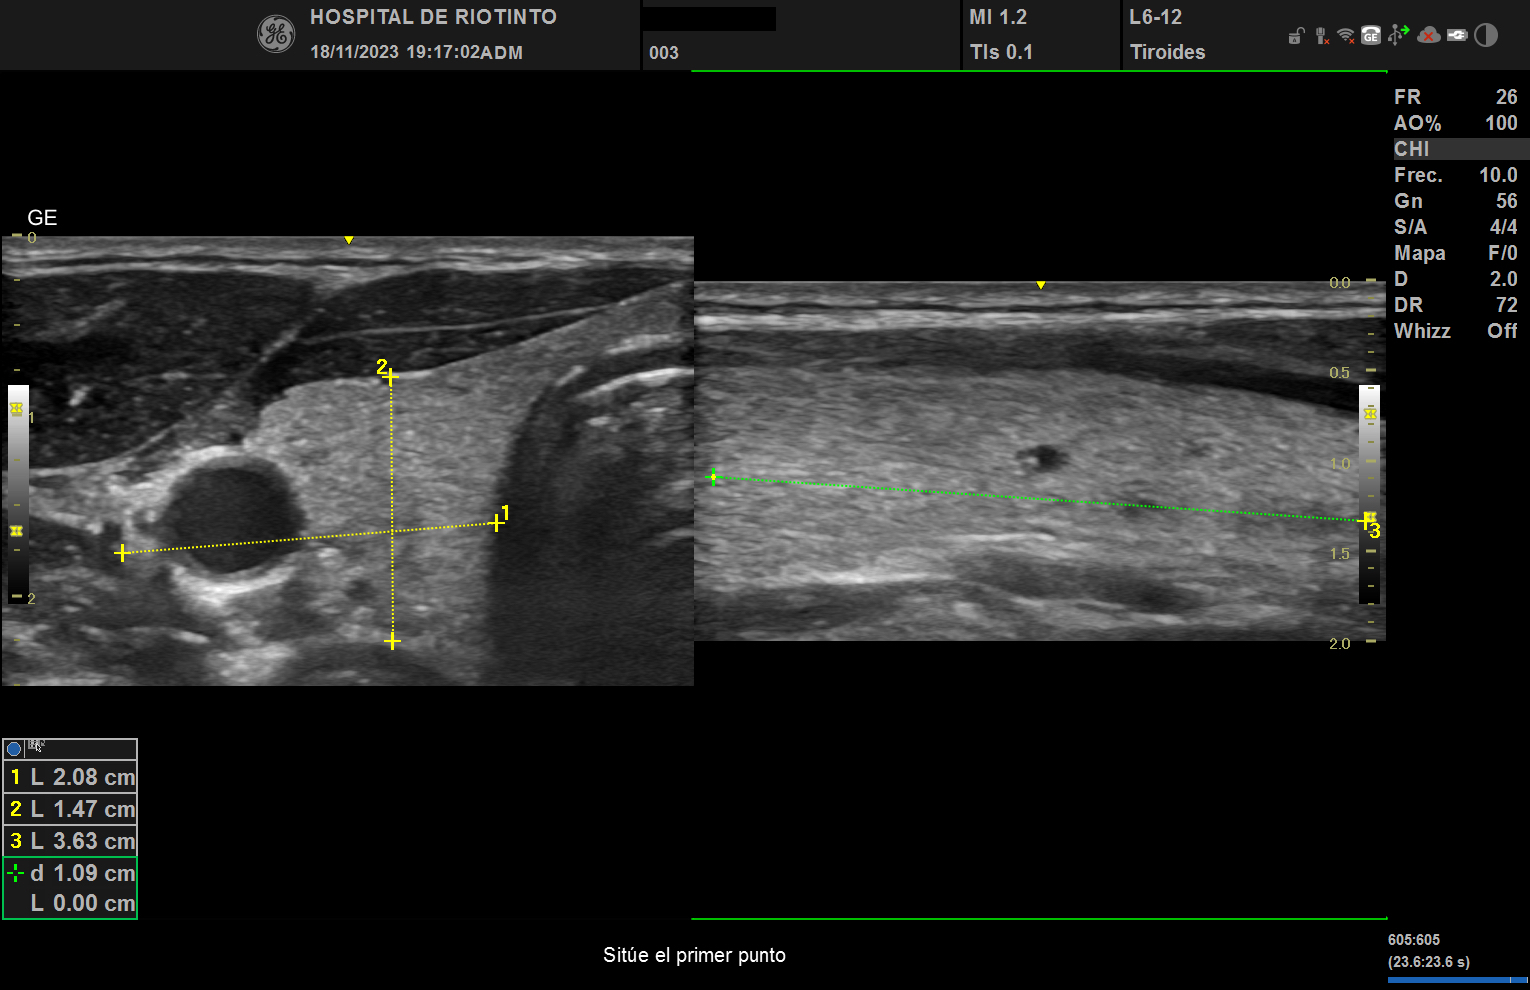

Se realizó ecografía en servicio de urgencias el cual encontramos los siguientes hallazgos:

Nódulo en polo inferior de lóbulo izquierdo de aproximadamente 2.08 X 1.47 x 3.63 cm de características de morfologías: con longitud mas alto que ancho, se observa trabéculas heterogéneas, visualizacion de leve vascularización sin evidencias de adenopatías colindantes, no se aprecia efecto masa en estructuras colindantes.